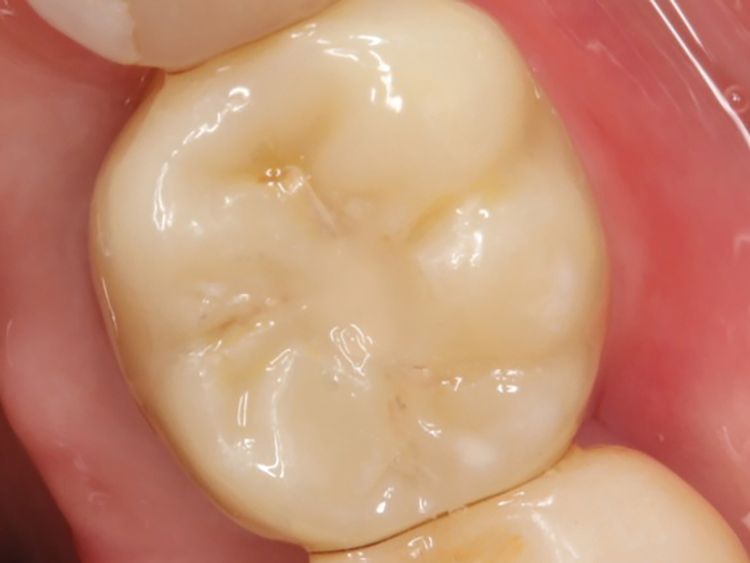

Following the healing period, a scan body was placed, and scan data were acquired to fabricate a new screw-retained, implant-supported restoration using a digital protocol (Figure 8). The patient returned, and after verification using a 3D printed model (Figure 9) and try-in, the restoration was delivered, and the prosthetic screw was torqued to the appropriate value. To block the screw channel, a piece of PTFE tape was placed over the prosthetic screw head to protect it; a universal bonding agent was applied to the occlusal third of the channel, air thinned, and light cured; and then a universal composite was placed, which provided an esthetic final result (Figure 10).